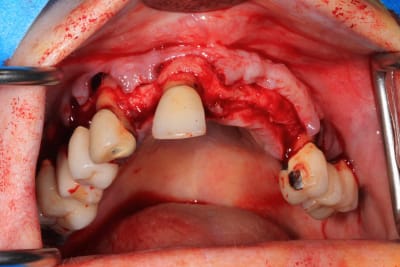

Le cas N°2 en images reelles :)

Guide métal avec support clavette, os assez fin : il est prévu un sticky bone complet : donc : lambeau avant extraction, positionnement du guide base et forage des clavettes, positionnement du guide implant, pose des piliers MU, controle des axes prothétique avec le guide pilier, collage des piliers prov sur le bridge a armature métal, occlusion nickel, sticky bone et PRF, sutures suspendues.

Voilà les photos du cas , avec un peu de retard.